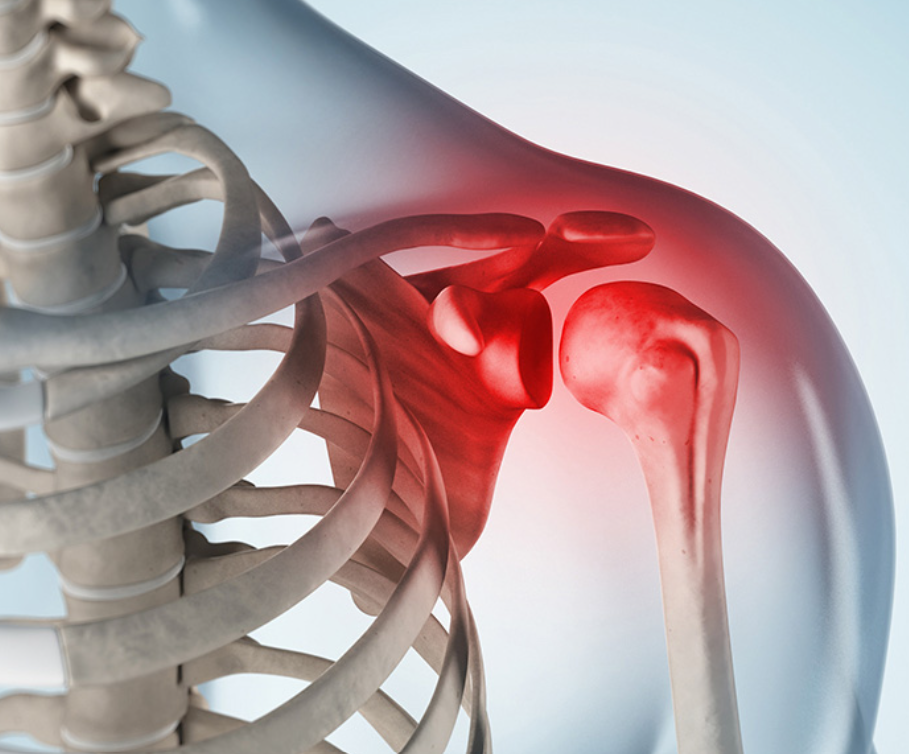

어깨통증 원인 3. 유착성 관절낭염

어깨통증 원인 세 번째는 유착성 관절낭염입니다. 팔을 움직일 때 어깨 통증이 느껴진다면 유착성 관절염 또한 의심할 수 있습니다. 유착성 관절염은 어깨 관절 주변의 막인 "피막"이 염증으로 인해 두꺼워지고 딱딱해져서 움직임이 제한되는 질환입니다. 유착성 관절염은 어깨 관절의 가동 범위를 감소시켜 팔을 들기 어렵게 하고 어깨 주변에 통증을 유발할 수 있습니다. 유착성 관절염이 진행됨에 따라 팔을 펴거나 구부리는 것과 같은 대부분의 움직임이 제한되고 어깨가 경직될 수 있습니다.

이 때는 아무리 힘을 써도 억지로 팔이 올라가지 않기 때문에 어떤 이유로 이러한 질병이 나타났는지 이유를 파악하는 것이 중요합니다. 이 때는 전문병원을 통하여 MRI와 초음파를 활용한 정밀검사를 실시하며 원인을 파악하여 원인을 개선하는 치료를 하거나 노화나 오십견으로 인한 통증인 경우 생활습관 개선, 약물치료, 재활 운동 등을 통하여 비수술적 치료를 우선적으로 실시하며 개선되지 않는다면 수술적 치료가 고려됩니다.